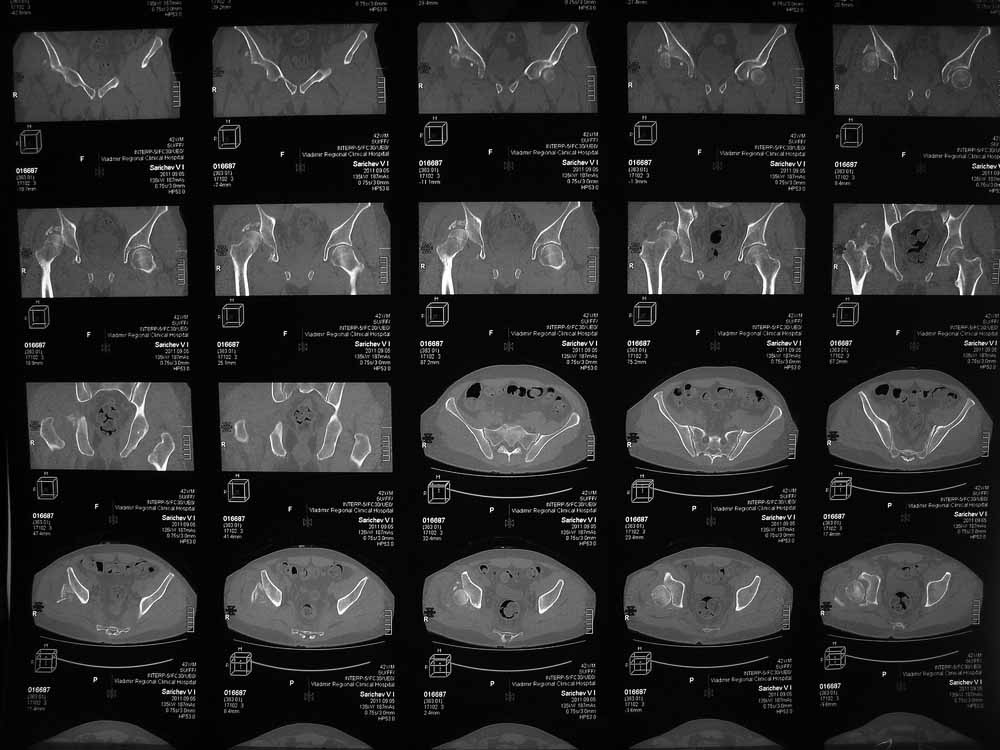

42 года, майор запаса. Травма от 20.06 - ДТП. Лечился в гражданском ЛПУ. Вывих бедра диагностирован только 4 недели спустя. "Тянулся", неоднократно - попытки закрытой репозиции. Попытка открытой репозиции - без результата. Потом опять пытались закрыто, сказали, что вправили, тянулся. После снятия ССВ - опять вывих. Поступил к нам. Сейчас - СРБ больше 10, в ОАК - воспаление. Местно - головка кзади и кверху, укорочение 7, голова подвижна. Отек, незначительная боль в в/3 бедра. Пассивно из наружной ротации выводится, активных движений в ноге нет. Рубец по наружной поверхности верхней трети бедра, без воспаления. Каким образом выполнялось открытое вправление - данных нет. Окончательно снят с вытяжения 2 недели назад.

Структуру головки не очень хорошо видно, есть перелом нижнего отдела головки БК, сломанный задний край небольшой. Срок после травмы 4 недели, молодой возраст. Есть смысл синтезировать ВВ, а дальше посмотреть. Будут проблемы - легче будет протез ставить, ну а если лет 8-10 сустав поработает, то и это хорошо. Если вы уж решили делать протезирование, не мудрите, вполне можно обойтись стандартной вертлужной впадиной с укреплением ее винтами.

Вот еще сканы.

В этой ситуации предпочел бы эндопротез, шансы на жизнеспособность головки в таком сроке вывиха исчезающе малы, попытка синтезировать задний край в этих же сроках (ретракция мышц, рубцы) скорее всего приведут к его девитализации с последующим аваскулярным некрозом. Выбор вертлужного компонента проще планировать после 3D, скорее всего можно будет обойтись стандартными предложением, возможно, с котилопластикой.